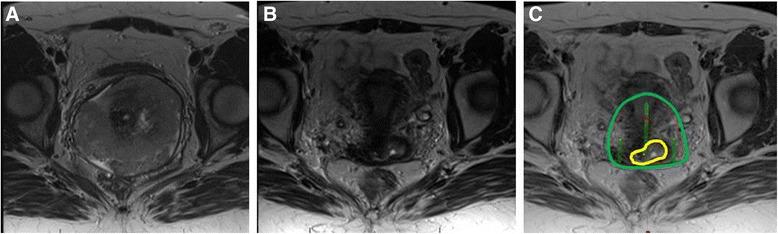

A practical review of magnetic resonance imaging for the evaluation and management of cervical cancer.

Cervical cancer is a leading cause of mortality in women worldwide. Staging and management of cervical cancer has for many years been based on clinical exam and basic imaging such as intravenous pyelogram and x-ray. Unfortunately, despite advances in radiotherapy and the inclusion of chemotherapy in the standard plan for locally advanced disease, local control has been unsatisfactory. This situation has changed only recently with the increasing implementation of magnetic resonance image (MRI)-guided brachytherapy. The purpose of this article is therefore to provide an overview of the benefits of MRI in the evaluation and management of cervical cancer for both external beam radiotherapy and brachytherapy and to provide a practical approach if access to MRI is limited.